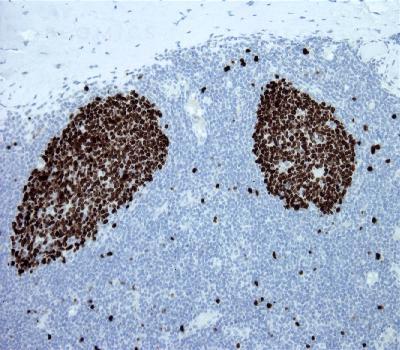

Figure-1: Tonsil section has been stained using Ki67 antibody (Clone: BS4) with 1:200 dilution. Majority of the germinal center B cells have strong nuclear label.

Ki67, also known as MKI67, is aprototypic cell cycle related nuclear protein, expressed by proliferating cells in all phases of the active cell cycle (G1, S, G2 and M phase). It is absent in resting (G0) cells. Ki67 antibodies are useful in establishing the cell growing fraction in neoplasms (immunohistochemically quantified by determining the number of Ki67 positive cells among the total number of resting cells = Ki67 index). In neoplastic tissues the prognostic value is comparable to the tritiated thymidine labelling index. The correlation between low Ki67 index and histologically low grade tumours is strong. Ki67 is routinely used as a neuronal marker of cell cycling and proliferation

Immunohistochemical Analysis :-1:200